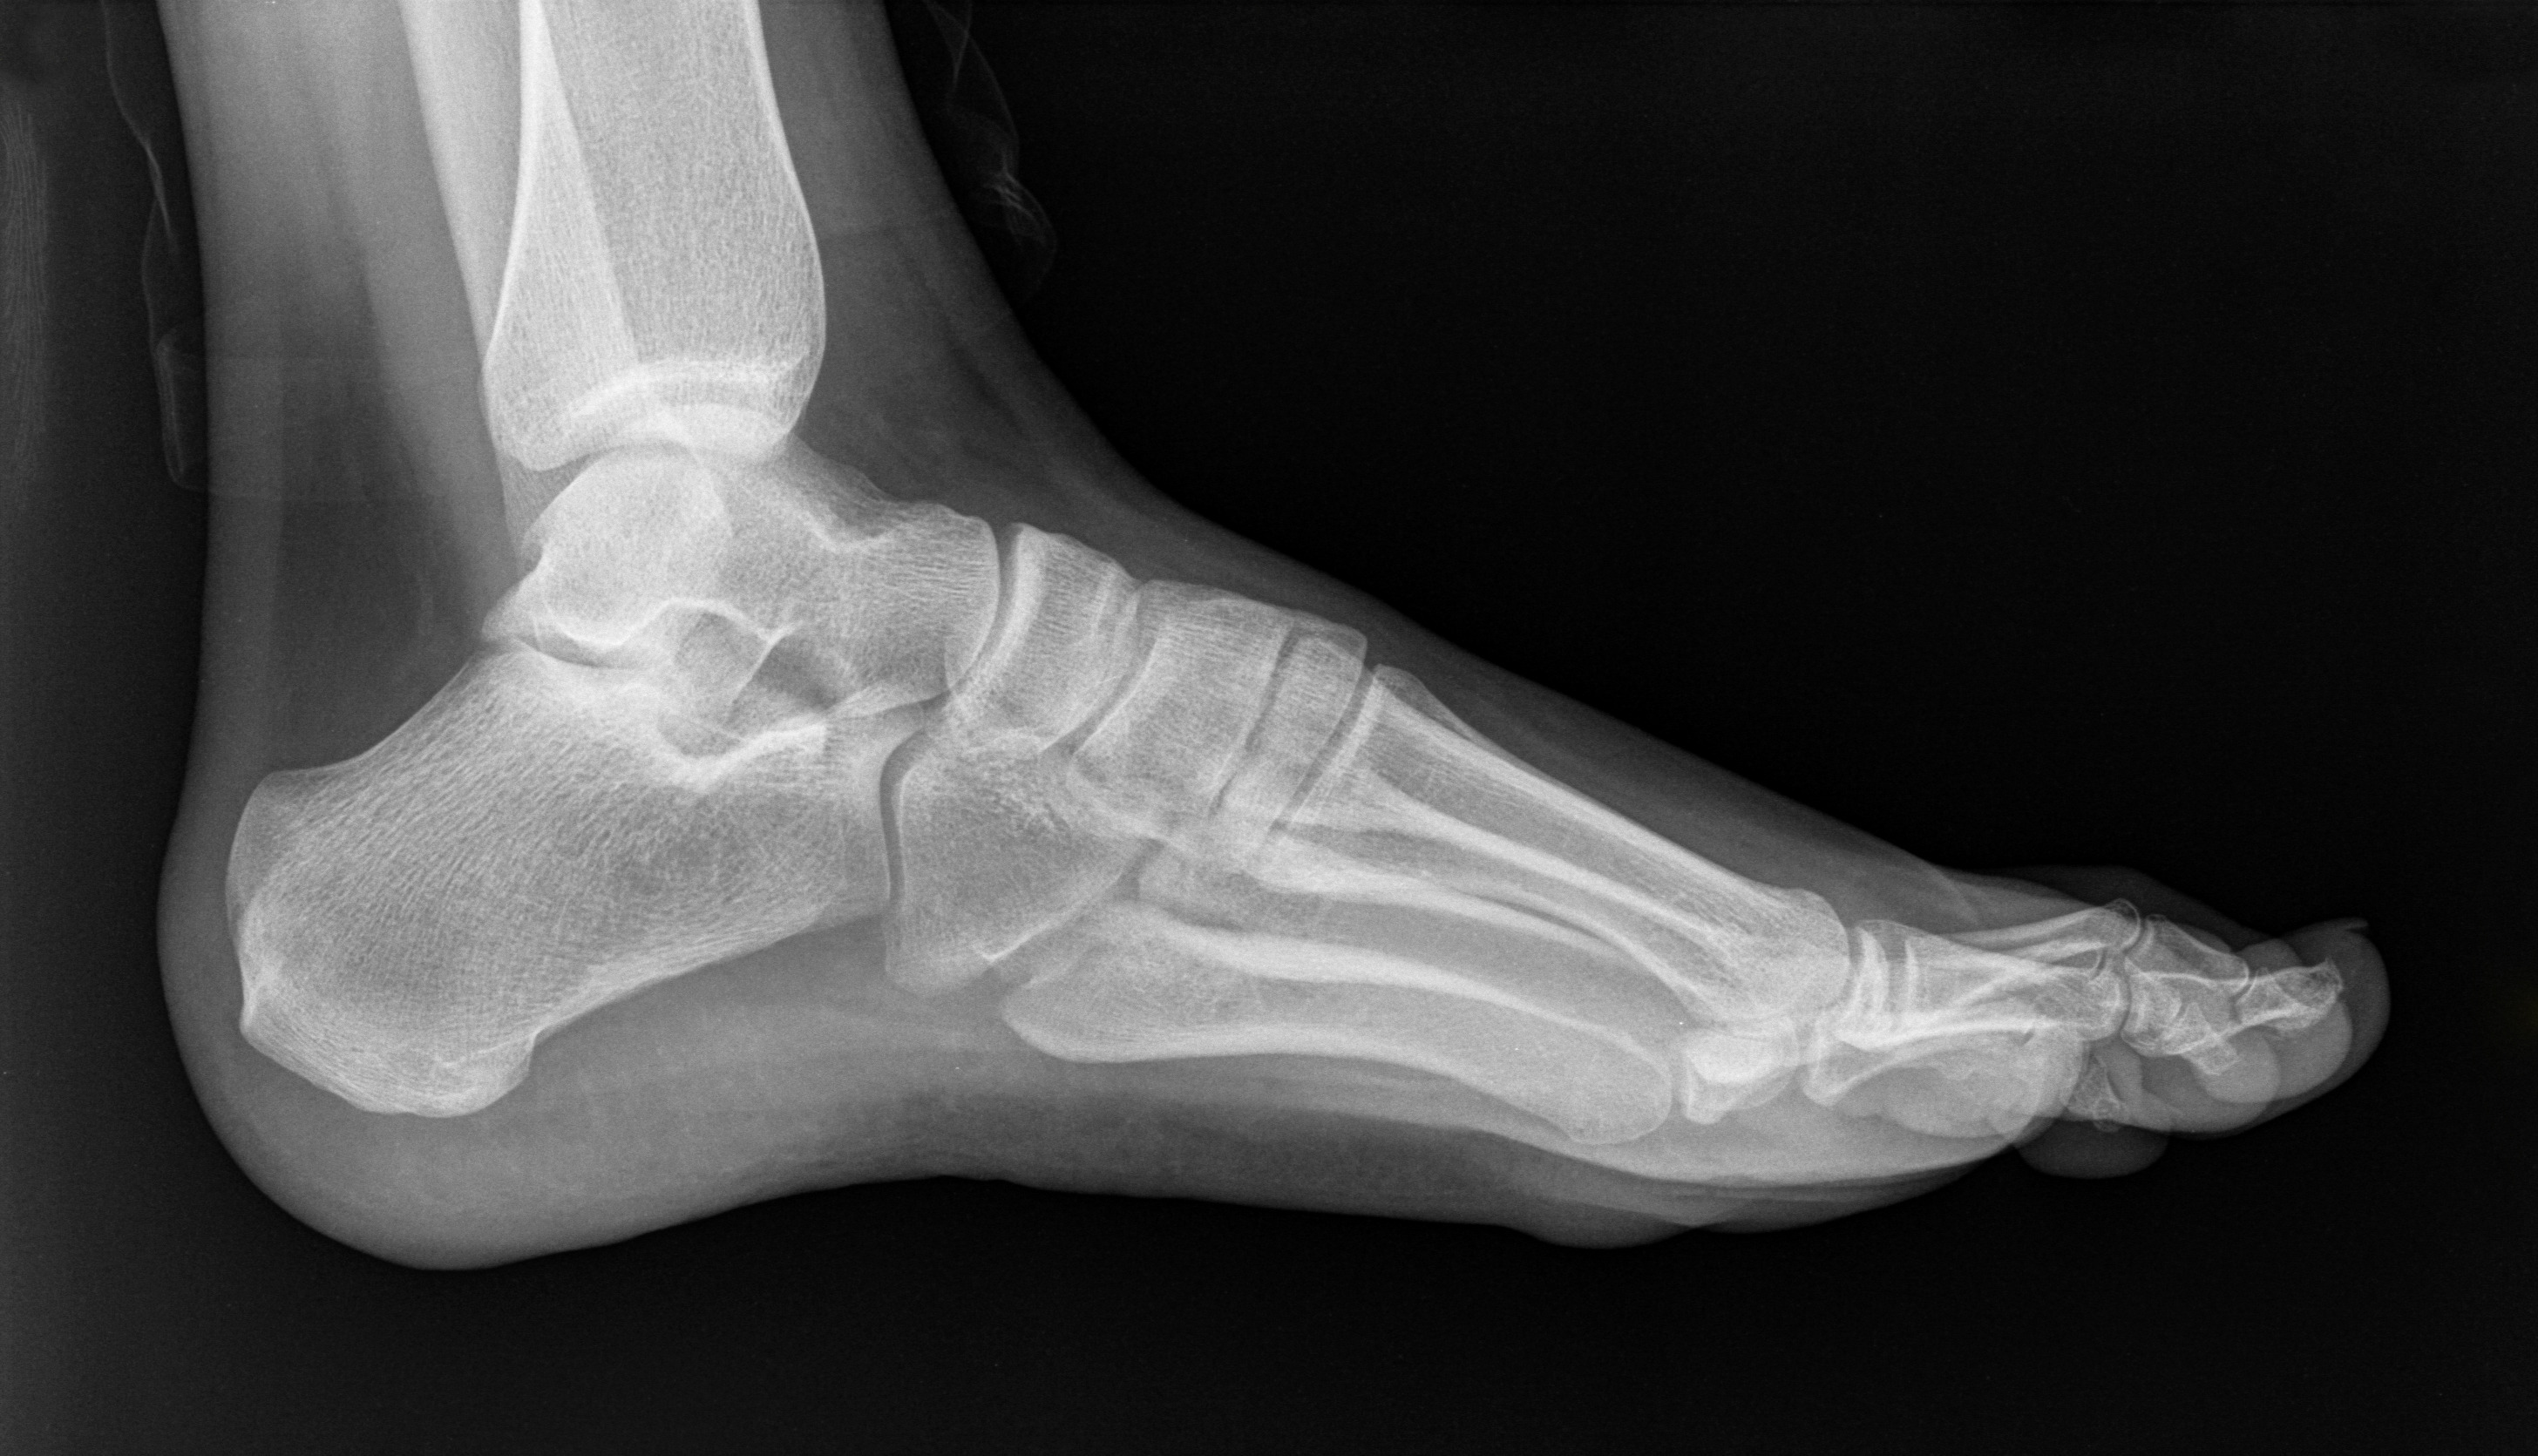

Сокращение светового дня снижает синтез витамина D в организме. Он необходим для укрепления костей. Если его не хватает, то риск переломов значительно увеличивается.